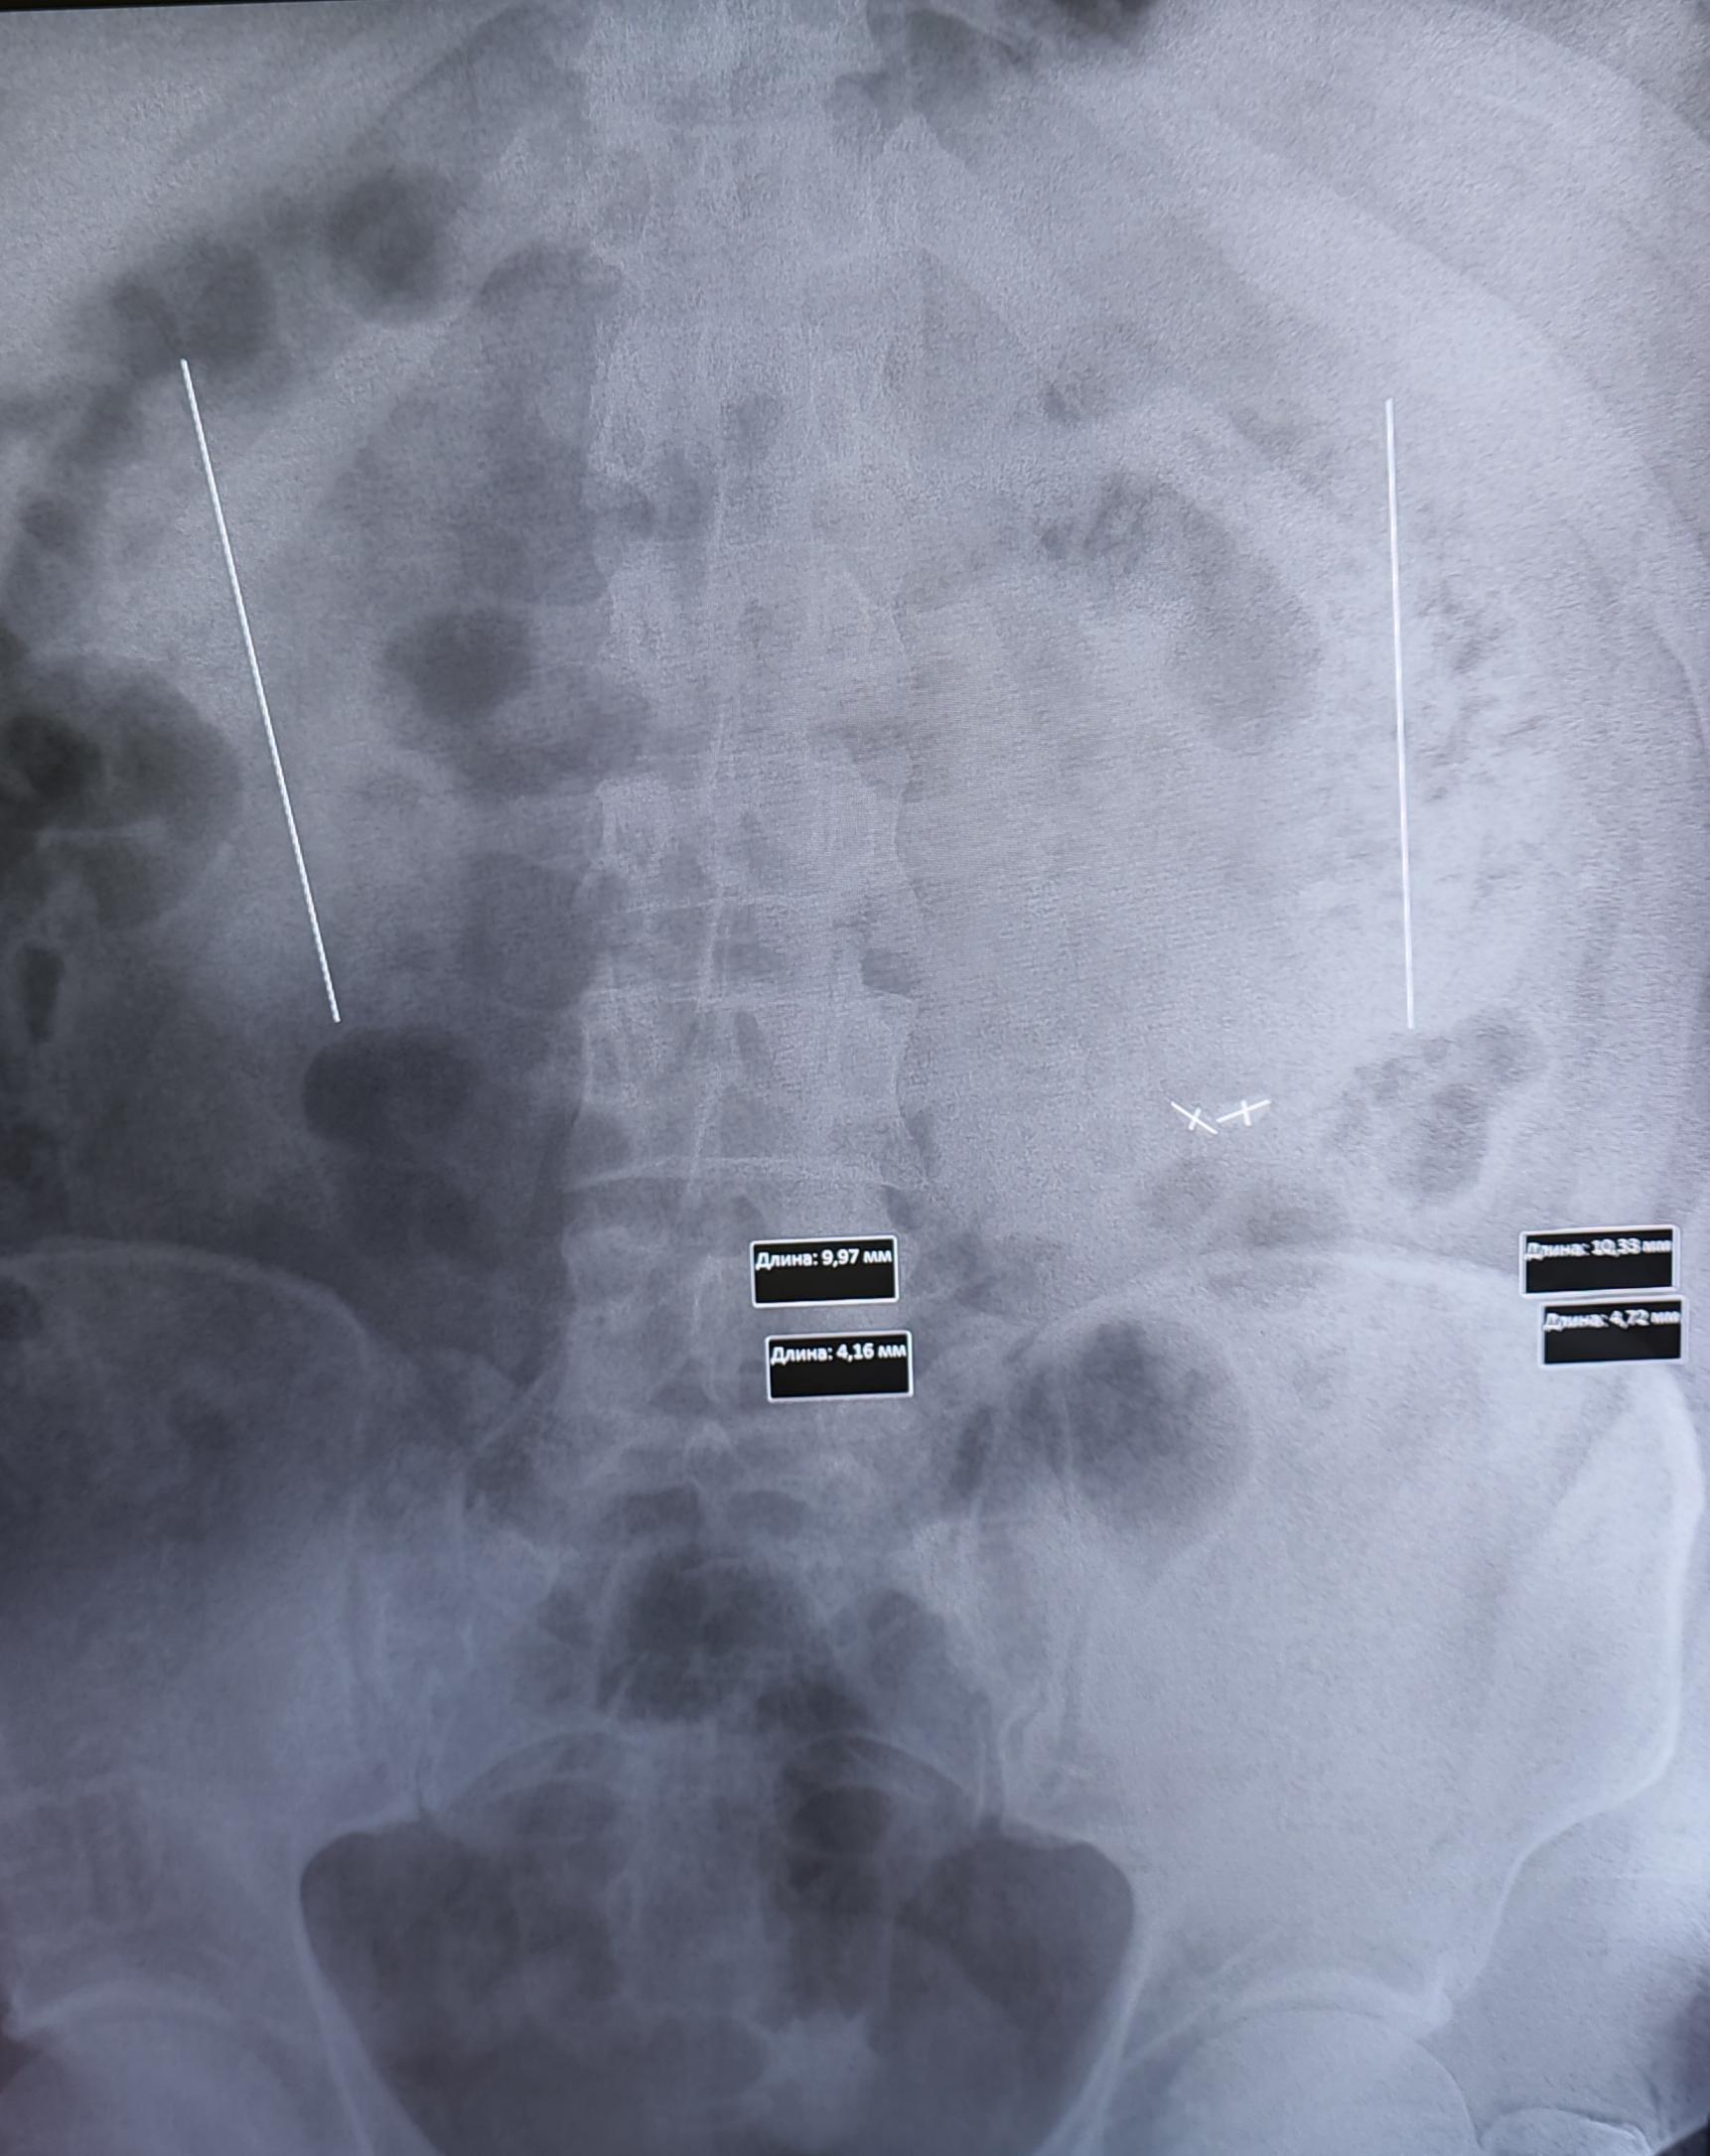

Описание: тени почек на уровне L1-L4 левая,L1-L4 правая, в ЧЛС левой почки определяются тени от множественных мелких конкрементов. В верхней трети левого мочеточника, ориентировочно 7.5мм от устья, визуализируются тени(N 2) от конкрементов, неправильной овальной формы, косо-горизонтально расположенные относительно мочеточника, размерами 10.3х4.7мм, 9.9х4.1мм.Заключение:Мочекаменная болезнь левой почки. Конкременты верхней трети левого мочеточника.